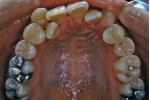

日本矯正歯科学会専門医課題症例(第4症例)

カテゴリー:ClassⅡ division 2 malocclusion (Overbite 5mm以上; 抜歯症例)

出題基準:大臼歯関係がclass Ⅱで、上顎中切歯1本を含む2本以上が舌側傾斜(U1-SN 90度以下)、犬歯関係もclass Ⅱであること。ただし、日本人では症例が少ないことを考慮して、U1-SN 100度以下のclass Ⅱ過蓋咬合も認める。抜歯・非抜歯は問わない。

出題の意味:このケースの条件は一般の人には理解しにくいところがある。通常出っ歯というと上の前歯が外に向かっていることを想像するのが普通であるが、U1-SNが90度以下というのは、上の前歯は内側に傾いていることを示している。なんで??。つまりこれは骨格性上顎前突と考えられるもので、上顎が歯並びごと全体が前へ出ていて、それだと上下の前歯があまりにも離れてしまうため、上の前歯が内側に倒れて下の前歯と何とか接触しようとしている状態と考えられる。

しかし、出題基準にも書いてあるように、このケースは欧米の白人によく見られるケースで、東洋人にはきわめて稀である。そこで類似ケースとして過蓋咬合(かがいこうごう)のケースを代替えとして認めるという配慮をしている。過蓋咬合とは非常に強く深く咬んでいる状態を言う。Overbiteとは前歯の垂直的な重なり具合を示す数値で、5mm以上だと上の前歯が下の前歯をほとんど覆い尽くしている感じになるので、前から見ると下の前歯はほとんど見えない状態になる。こういう状態が典型的な過蓋咬合である。典型的なclassⅡ,division 2のケースは過蓋咬合を合併している。

| 初診時